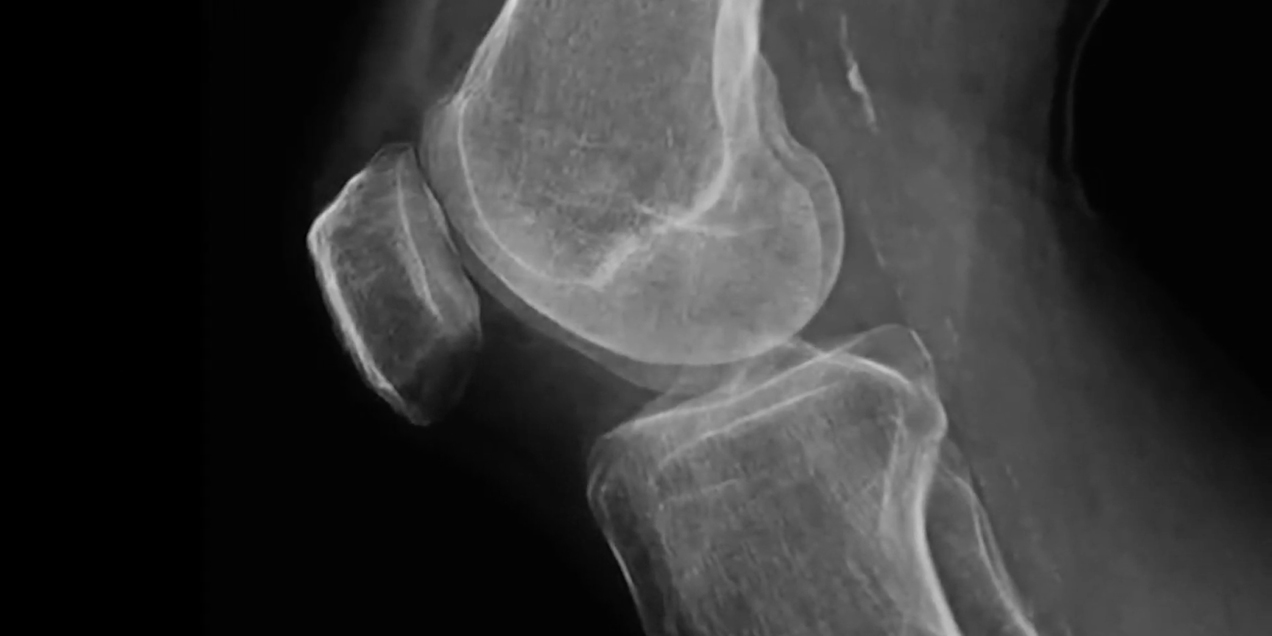

MRI image of the knee highlighting bony anatomy and joint surfaces used for musculoskeletal imaging analysis.

The Clinical and Translational Musculoskeletal Imaging (CTMI) group focuses on advancing standard and emerging imaging techniques to better understand diseases of the musculoskeletal system, with a primary emphasis on osteoarthritis. The lab develops and applies imaging biomarkers to assess disease severity, monitor progression, and identify early structural and biochemical changes in joints using MRI based approaches.

The team has created widely used quantitative and semi quantitative tools, including Whole Organ MRI Scores of the knee, composite measures of synovitis, and the SHOMRI system for hip osteoarthritis. In parallel, the lab develops artificial intelligence based methods to quantify muscle volume, fat infiltration, periarticular adipose tissue, and synovitis, as well as explores innovative imaging approaches such as low field MRI at 0.55T, metal artifact reduction techniques, and CT like MRI.